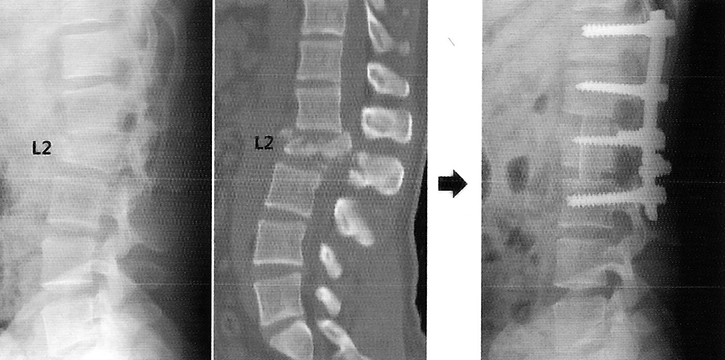

Рентгеновские снимки и медицинские изображения компрессионных переломов